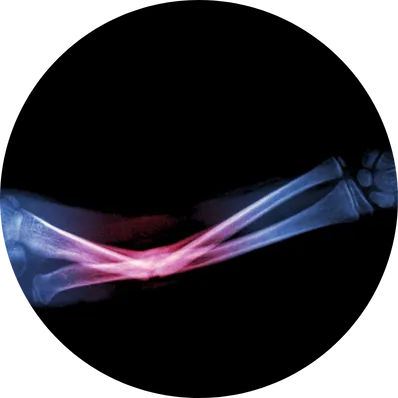

Forearm plating surgery is an orthopedic procedure used to treat fractures of the radius, ulna, or both bones in the forearm. Metal plates and screws are surgically fixed to the bone to provide stability, ensure proper alignment, and allow the bone to heal correctly. This procedure is commonly performed in displaced, unstable, or complex fractures where casting alone is insufficient.

Healic specialists suggest plating when you have severe pain, visible deformity, inability to rotate the arm, open fractures, or fractures that cannot heal properly with casting alone.